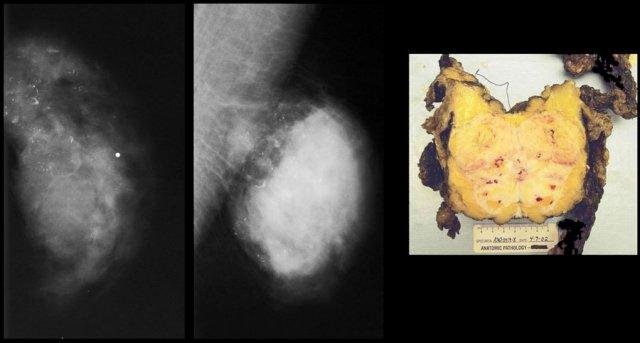

Bên trái là hai trường hợp minh họa cho thấy việc phân biệt vú nam to với ung thư biểu mô trên nhũ ảnh có thể rất khó khăn.

Ung thư biểu mô ở bên phải có bờ được bao bọc rõ hơn một chút so với vú nam to ở bên phải.

Trong chưa đến 10% các trường hợp, cần sinh thiết để phân biệt hai thực thể này.

Bên trái là thêm hai trường hợp nữa.

Ở ngoài cùng bên trái là hình ảnh vú nam to lan tỏa.

Bên phải là một khối ung thư lớn có bờ được bao bọc.

Các trường hợp cuối cùng ở bên trái trông rất giống nhau.

Dựa trên nhũ ảnh, không thể phân biệt được hai trường hợp này.

Trong những tình huống hiếm gặp như vậy, cần phải tiến hành sinh thiết.